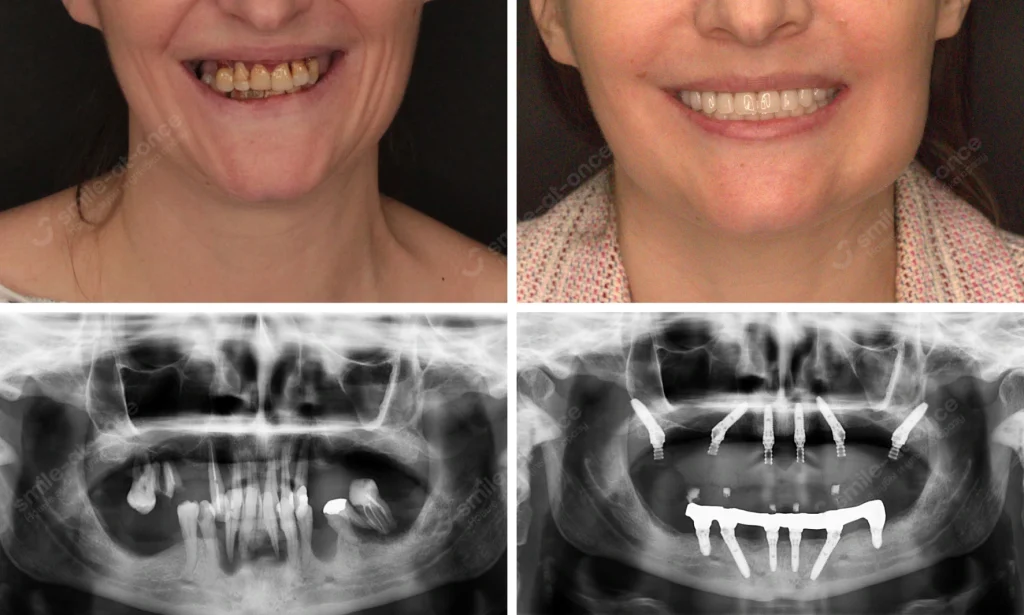

Хирургический этап и немедленная нагрузка

Если мы восстанавливаем целую челюсть, часто применяю All-on-4 / All-on-6 с немедленной нагрузкой: импланты ставлю за один визит (под анестезией, максимально щадяще), и в ближайшие дни фиксирую адаптационный протез. Он бывает двух типов — бескаркасный временный из акрила (PMMA) или каркасный (металлопластмасса). Выбор зависит от качества кости, прикуса, бруксизма и вашей задачи: «поскорее выйти в люди» или «сразу пожёстче пожевать».

- Полная адентия, атрофия кости: All-on-4 с немедленной нагрузкой; адаптационный металлопластмассовый протез → через 8–12 мес цирконий/металлокерамика.